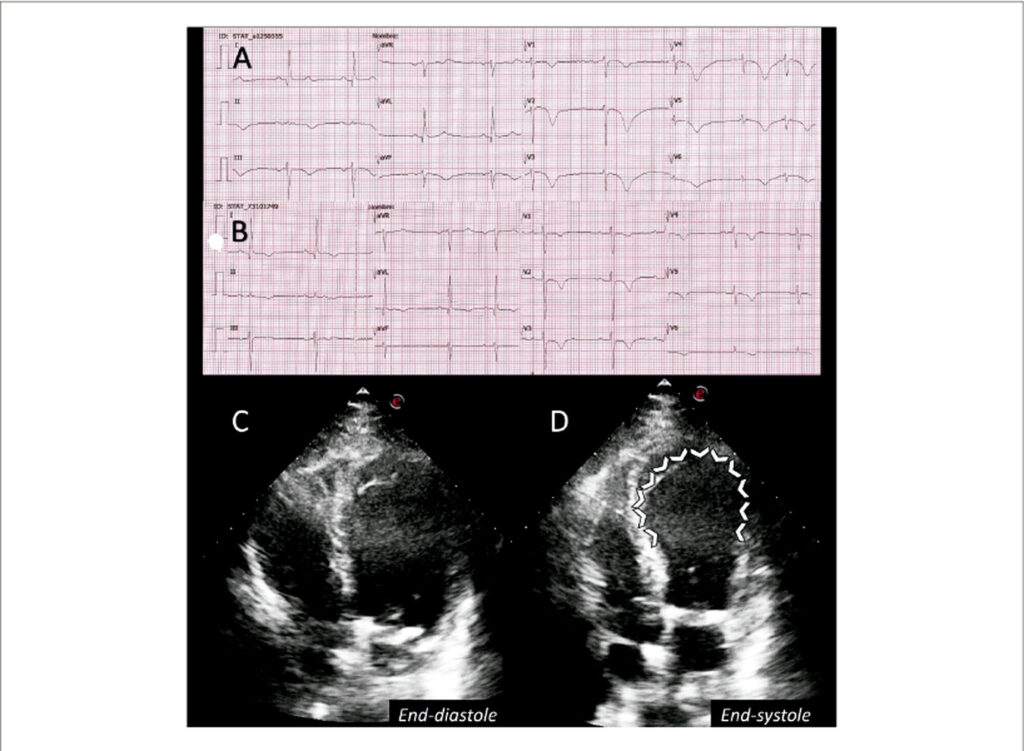

Takotsubo Syndrome in a Critical COVID-19 Patient: Electrocardiographic and Echocardiographic Evolution

By resembling a Japanese traditional octopus trap, i.e. a takotsubo, Hikaru Sato described the first case of “Takotsubo cardiomyopathy” in a patient without coronary stenosis and end-systolic left ventricular apical ballooning on a cardiac left ventriculography.Takotsubo syndrome (TTS) is a clinical syndrome characterized by an acute and transient left ventricular systolic dysfunction related to an emotional or physical stressful event. COVID-19 is a recognized trigger for TTS, with the possible explanations being the enormous emotional stress caused by the pandemic and the entire spectrum of myocardial damage associated with SARS-COV-2.